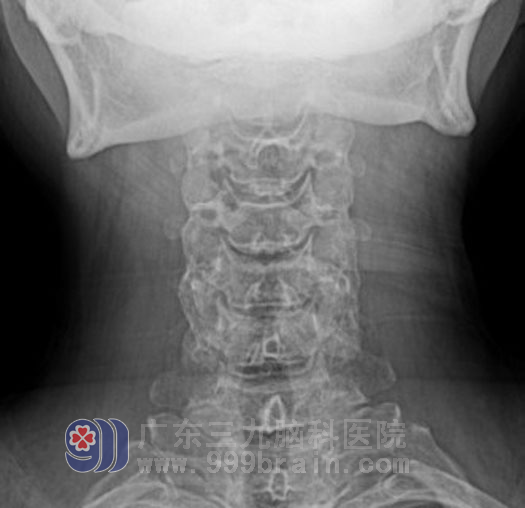

倪莹莹主任和邱承尧主治医生为她安排了针对性的临床检查,并请首席外科专家黄勤教授阅片把关排除垂体瘤复发。最后颈椎片的特异表现,引起了专家的注意,在第4-5颈椎右侧钩椎关节像鱼刺样变尖,相应椎间孔明显变窄,另外临床还有一个非常少见的特点,每当头痛发作病人通过进食一些热稀饭或热糊状食物,疼痛就能缓解,于是专家分析这是因为增生的骨刺反复刺激深部颈肌导致局部组织水肿,粘连,血管痉挛,而颈肌深部血管神经与咽喉相毗邻,口腔咽喉持久的温热刺激可以松解痉挛的血管和肌肉,从而缓解疼痛,思路明确了,就有了对策。

第4-5颈椎右侧钩椎关节像鱼刺样变尖

第4-5颈椎间孔明显变窄